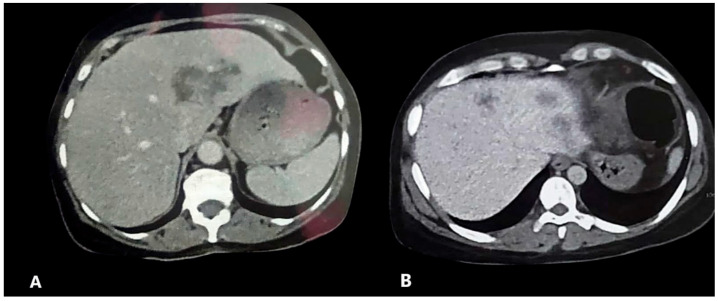

三氯苯达唑(TCBZ)是治疗片形吸虫病的金标准。然而,关于耐药性的报道越来越多,强调了替代治疗的必要性。TCBZ联合伊维菌素(IVM)治疗动物片形吸虫病疗效显著。在此基础上,我们旨在评估TCBZ/IVM联合治疗人片形吸虫病的疗效。本研究招募了来自上埃及的136例片形吸虫患者,他们被分为第一组(n = 65),接受TCBZ单药治疗,第二组(n = 71),接受TCBZ/IVM联合治疗。评估是基于临床、嗜酸性粒细胞和放射学参数来评估治疗反应。慢性筋膜吸虫病17例(12.5%)。在年龄和性别方面没有观察到差异。两组的所有参数均有显著改善,第二组的效果更明显。联合治疗组有更高的完全缓解,包括临床、嗜酸性粒细胞和放射学的改善,达到53.3%,而单药治疗组为26.2% (p < 0.001)。高基线嗜酸性粒细胞计数与反应显著相关。TCBZ/IVM联合治疗人片形吸虫病的疗效提示可能有促进作用,可以使TCBZ失效的区域受益。需要进一步的大规模随机研究来证实这些发现。

Triclabendazole (TCBZ) is the gold standard treatment for fascioliasis. However, reports on resistance are increasing, emphasizing the need for alternative therapy. Combining TCBZ with ivermectin (IVM) was found to be effective for treating animal fascioliasis. Building on this, we aimed to evaluate the efficacy of the TCBZ/IVM combination therapy for human fascioliasis. This study enrolled 136 patients with Fasciola from Upper Egypt, and they were divided into the first group (n = 65), who received TCBZ monotherapy, and the second group (n = 71), who received the TCBZ/IVM combination. Assessments were to evaluate treatment response based on clinical, eosinophilic, and radiological parameters. Chronic fasciolosis was diagnosed in 17 patients (12.5%). No differences were observed in age and sex. Significant improvements were noted in all parameters in both groups, with more pronounced effects observed in the second group. A significantly higher complete response, including clinical, eosinophilic, and radiological improvements, was reported in the combined therapy group, with 53.3% compared to 26.2% in the monotherapy group (p < 0.001). A high baseline eosinophilic count was significantly associated with response. The efficacy of the TCBZ/IVM combination for treating human fascioliasis suggested a possible boosting effect, which can benefit regions of TCBZ failure. Further large-scale randomized studies are warranted to confirm these findings.